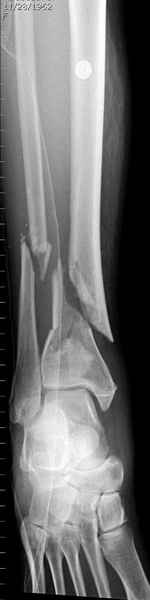

На снимках варианты фиксации малоберцовой:

№ 2-5 при огнестрельном переломе

DK> № 2-5 при огнестрельном переломе

Перелом оскольчатый с диастазом и нефиксация грозила бы ложным

суставом, здесь трудно не согласиться, но... осколок на место поставлен

не был... Вполне возможно, что все и сраслось, но... Никаких проблем в

данном конкретном случае не было? Болей там всяких, тендинитов etc?